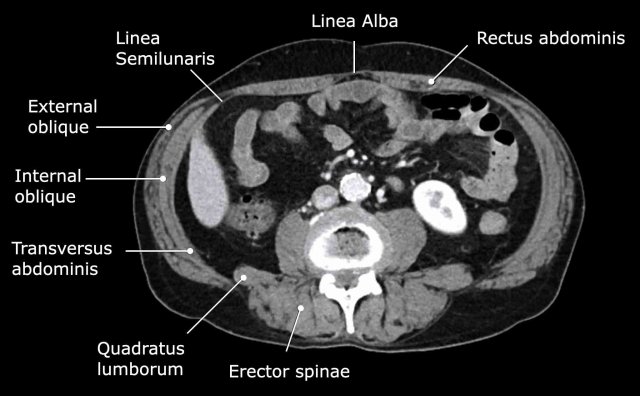

Abdominal wall musculature

Important muscular structures that surround the abdominal organs are shown in this figure.

The linea alba is a line formed by the aponeuroses of the right and left rectus muscle and connects both muscles in the midline.

As the linea alba is an avascular area, it is frequently used as point of entrance for open abdominal surgery.

The linea semilunaris is a curved tendinous line that is located lateral to the rectus abdominis muscle on both sides.

Here, the anterior and posterior rectus sheaths connect with the three lateral abdominal wall muscles: the external oblique, the internal oblique and the transverse abdominal.